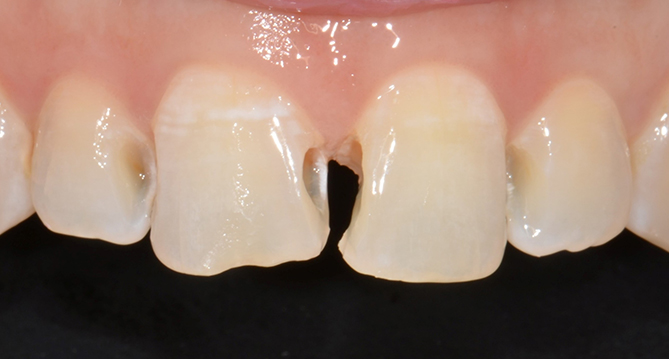

치아의 기능과 심미성 회복을 위한 치료로

정확한 치료계획이 필요한 보철치료

보철과 전문의의 자연치아보호하기, 금이 갔거나 심한 충치로 인해

상실 또는 손상된 치아를 견고하고 심미적인 보철물을 통해 기능과 심미성 회복을 도와줍니다.

심미성이 중요한 전치부 보철물은 더욱 더 전문성이 필요합니다.

연세새빛치과는 보건복지부인증 보철과 전문의의 정확한 진단과

정석적이고 체계적인 치료를 진행합니다.